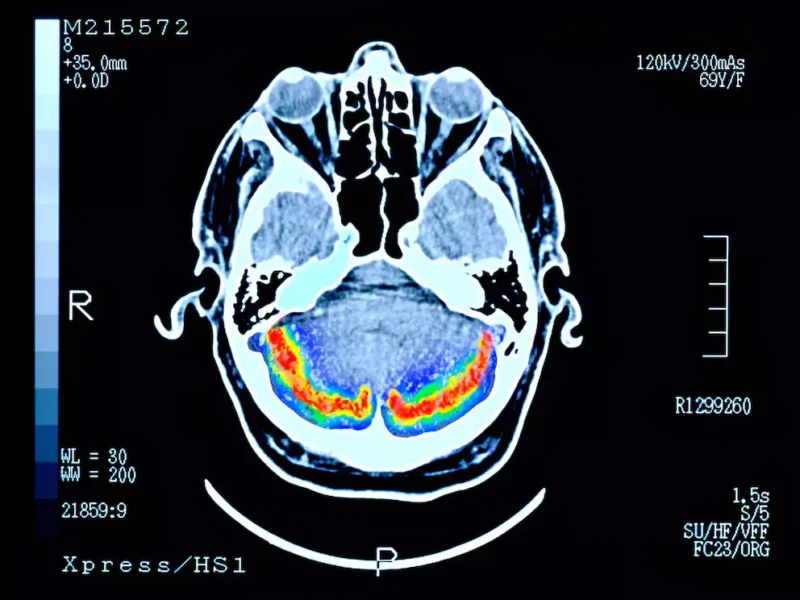

Se han identificado algunas proteínas anormales, como las placas beta amiloide y los ovillos neurofibrilares, que se acumulan en el cerebro y pueden causar la muerte de las neuronas.

El estudio publicado en la revista Frontiers in Aging Neuroscience, refiere que la proteína es una glicoproteína secretada por los astrocitos —células clave del sistema nervioso central—, de la cual ya se conocía su papel en el desarrollo del cerebro. Sin embargo, esta nueva investigación demostró que también tiene un rol fundamental en la reparación del tejido cerebral dañado por enfermedades neurodegenerativas.

En los ensayos con modelos animales, los especialistas aplicaron una forma recombinante de hevina directamente en el cerebro de ratones con síntomas similares a los del Alzheimer humano. Tras el tratamiento, se observó una recuperación significativa de las conexiones sinápticas y una mejora evidente en pruebas de memoria, actúa como un “pegamento” neuronal, facilitando la formación y el fortalecimiento de nuevas conexiones entre las neuronas.